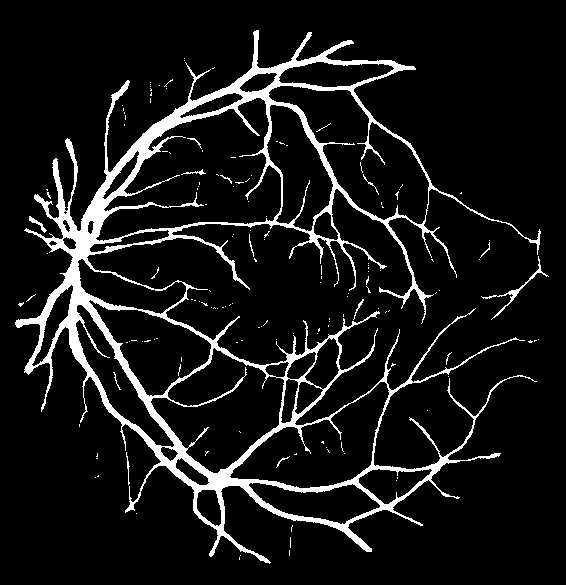

Figure 7: Visual results for two sample DRIVE images.

Results for DRIVE Test Images: Quantitative results of BLCB-CNN for all DRIVE images are computed, which shows that the proposed method achieves an average accuracy of 96.22. The average sensitivity/specificity value of 81.57/97.65 also indicates the model’s ability to accurately segment vessel pixels (including thin vessels). The AUC results are also consistent with the accuracy obtained for all the images. Figure 7 demonstrates the visual outcomes for two sample DRIVE images. It can be observed that the proposed method segmented both thin and thick vessels much closer to ground truth binary masks. This is further evident from the focused rectangular areas of the output/ground-truth images.